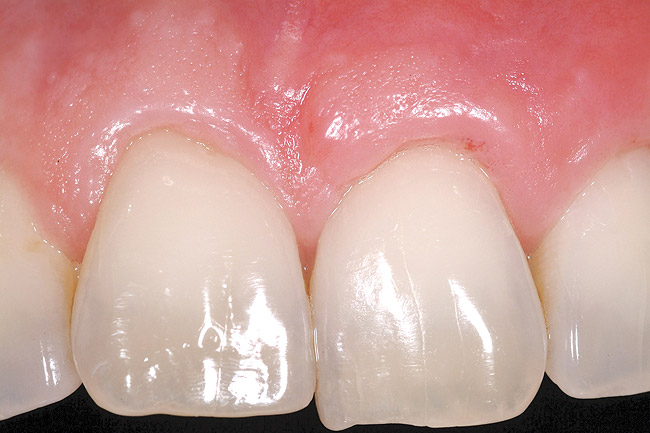

A 27-year-old non-smoking man presented for esthetic enhancement of the left central incisor, which had a pre-existing full-coverage restoration that required replacement (Figure 16). The patient had begun orthodontic treatment in the mandibular arch to correct a minor occlusal imbalance and required coronal repositioning and soft tissue grafting to correct gingival recession at the facial of the right canine, in addition to correction of the free gingival margin at the facial of the left central incisor, which was asymmetrical to the free gingival margin of tooth No. 8. Additionally, the facial gingival tissues were of a thin biotype, which at the facial surface of the left central incisor allowed for the darkened root surface to be visible through the tissue (Figure 16).

The treatment plan was to accomplish an increased zone of keratinized tissue at tooth No. 6, and increase the thickness of the facial tissue at tooth No. 9, in addition to coronally repositioning the free gingival margin. Complicating this treatment plan was the fact that at the facial surface of tooth No. 9, a biologic width invasion was present due to the prepared margin for the pre-existing restoration being placed too close to the facial alveolar crest of bone (the patient had presented to the periodontist with a provisional restoration in place). Any correction to the area would require movement of the facial margin of the tooth in a coronal fashion to re-establish the appropriate distance from the facial height of bone to the margin of the restoration. Additionally, options were given to the patient for harvesting the soft tissue, using connective tissue from the palate, or the use of an acellular dermal matrix graft, which would nullify harvesting tissue from the palate region.

Figure 20 shows the completed view with the final restoration seated. Observe the balance of the facial heights of contour between the central incisors, and the presence of a thick-biotype, attached keratinized tissue.

Figure 16  Case Two Preoperative clinical view, maxillary left central incisor.

Figure 16

Figure 20  Case Two Case Two, complete view.

Figure 20